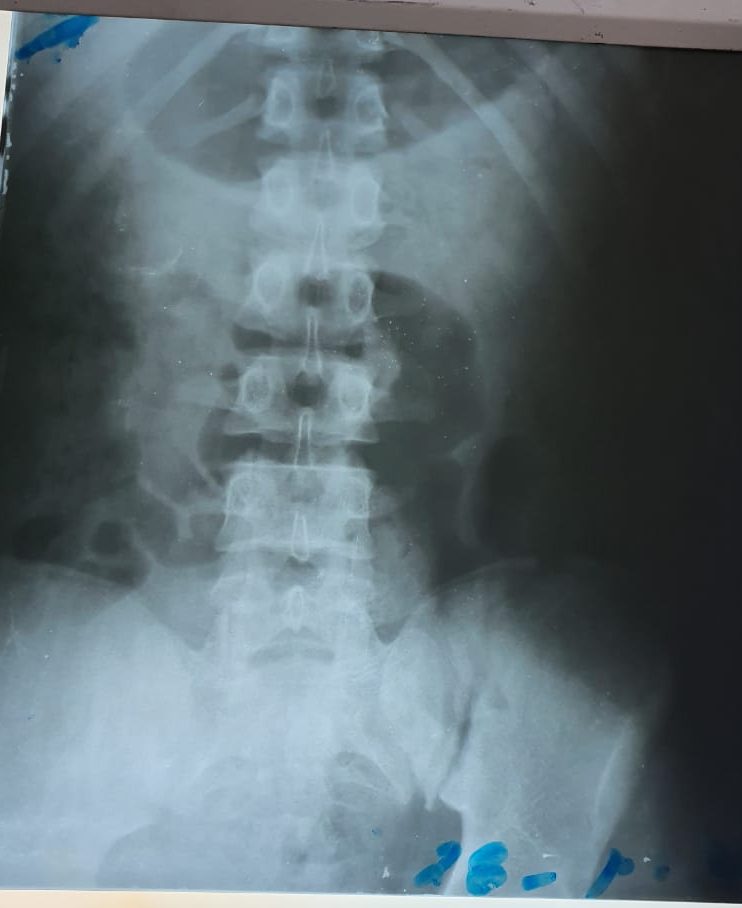

El diagnóstico final de los médicos es que el adolescente tiene la pelvis quebrada, esta a su vez afectó seriamente la uretra. Por ello necesita ser intervenido quirúrgicamente en Lima.